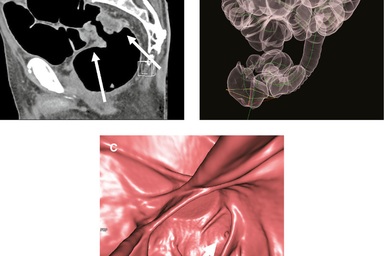

Căn bệnh ung thư gây tử vong thứ 2 đứng sau ung thư phổi. Tuy nhiên, nếu được tầm soát và phát hiện sớm thì tỉ lệ lành bệnh sẽ cao. Ung thư đại trực tràng là loại ung thư xảy ra khi những tế bào bất thường phát triển ở niêm mạc đại tràng và trực tràng.